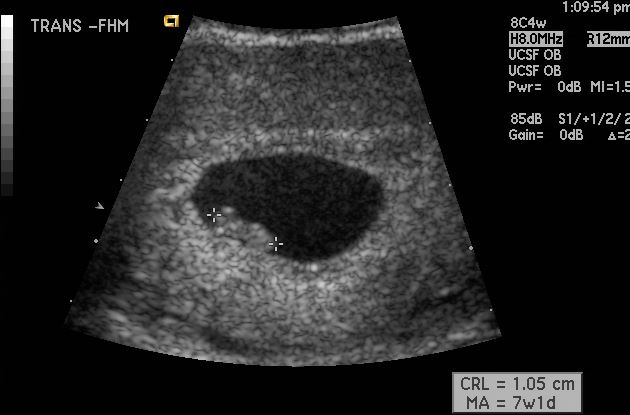

My Ultrasound Showed No Fetal Pole. Am I Miscarrying?

My Ultrasound Showed No Fetal Pole. Am I Miscar… 2. No Fetal Heartbeat on Early Ultrasound. Is… 3. How Do Doctors Diagnose Miscarriage and… 4. My Ultrasound Showed No Gestational Sac. What… 5. What Does It Mean When the Gestational Sac Is S… ... Read Article

Miscarriage / Pregnancy Loss Glossary - Definitions Of ...

Blighted ovum, chemical pregnancy, or spontaneous abortion. Our glossary includes thorough explanations of miscarriage terms in language that you can understand. In a pregnancy ultrasound, the CRL Miscarriage and Pregnancy Loss Glossary About Health Follow us: ... Read Article